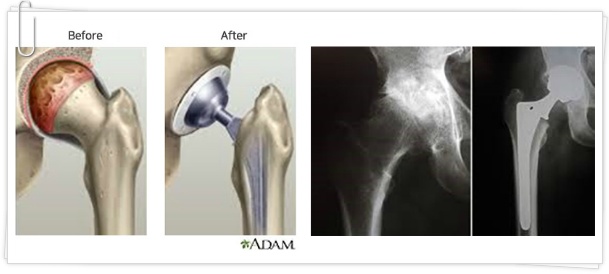

고관절 수술은 다양한 이유로 시행될 수 있지만, 일반적으로는 고관절 관절염, 외상, 또는 선천적인 기형 등으로 인해 통증이나 기능 저하가 나타날 때 이루어집니다. 이 수술에는 인공관절 치환술, 관절경 수술 등의 방법이 있으며, 각각의 수술 방법은 회복 단계와 필요한 시간에 서로 영향을 미칩니다. 고관절 수술의 주된 목적은 통증을 감소시키고, 이동성과 일상생활의 질을 향상시키는 것입니다. 그러므로, 환자는 수술 후 생활 습관을 조절하고, 적극적인 rehabilitative 간호를 통해 빠른 회복을 도모해야 합니다.

- 인공관절 치환술: 가장 일반적인 고관절 수술입니다. 퇴행성 관절염이나 심한 외상으로 인해 고관절이 손상된 경우, 인공 관절로 대체합니다. 이 수술은 대개 1-2시간 가량 소요되며, 회복이 길어질 수 있습니다.